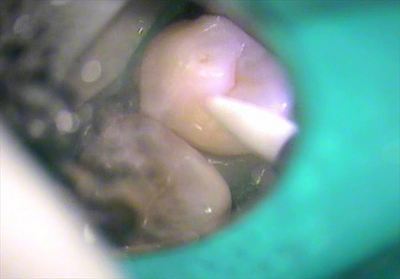

う蝕検知液で軟化象牙質を染色します。

やはり第一小臼歯の過去のレジンの内部はかなり染まります。